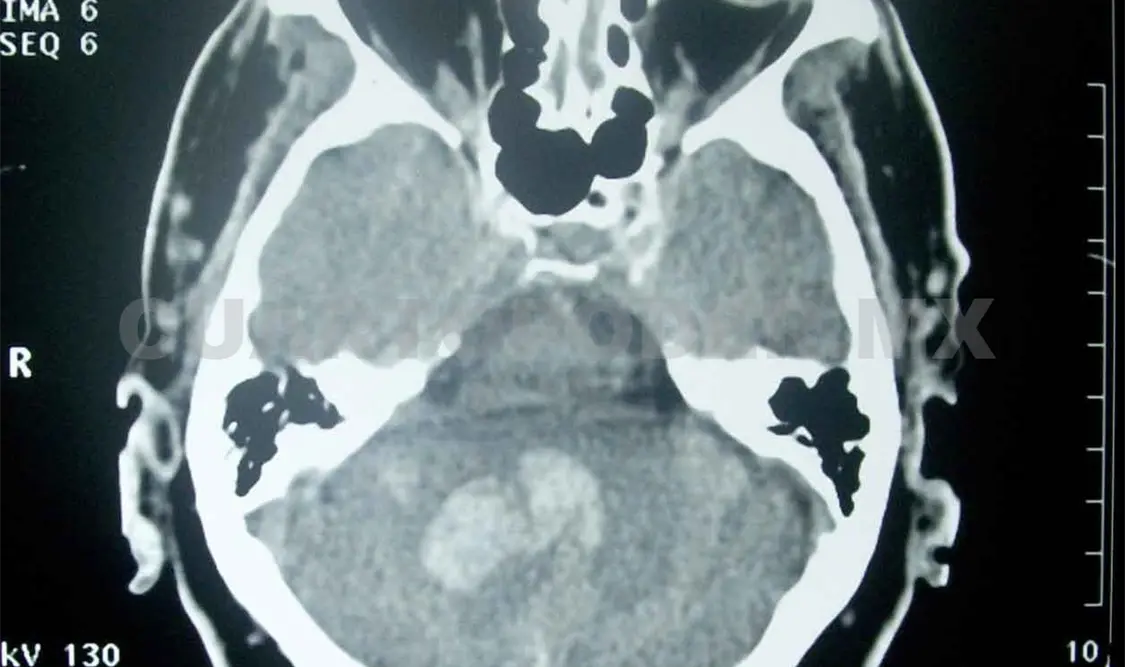

De acuerdo al Centro Nacional de Neurología y Neurocirugía “Manuel Velasco Suárez”, existen tres tipos de EVC: trombótico, embólico y hemorrágico; el primero se origina por los depósitos grasos en las arterias, lo que causa la formación de coágulos como consecuencia del estrechamiento de los vasos sanguíneos.

En el caso del EVC embólico, el coágulo se forma en otras partes alejadas del cuerpo, parte de esa formación conocida como “émbolo” es arrastrado hacia el cerebro hasta que tapa un vaso sanguíneo y corta el abastecimiento de sangre ocasionado una embolia.

Por último está el tipo hemorrágico o derrame cerebral, causado por la ruptura y sangrado de un vaso sanguíneo en el cerebro. En todos los casos las señales de alarma, además de las que enlistó doña María, son visión borrosa, mareos repentinos, dolor de cabeza intenso e incapacidad para comunicarse de cualquier forma.